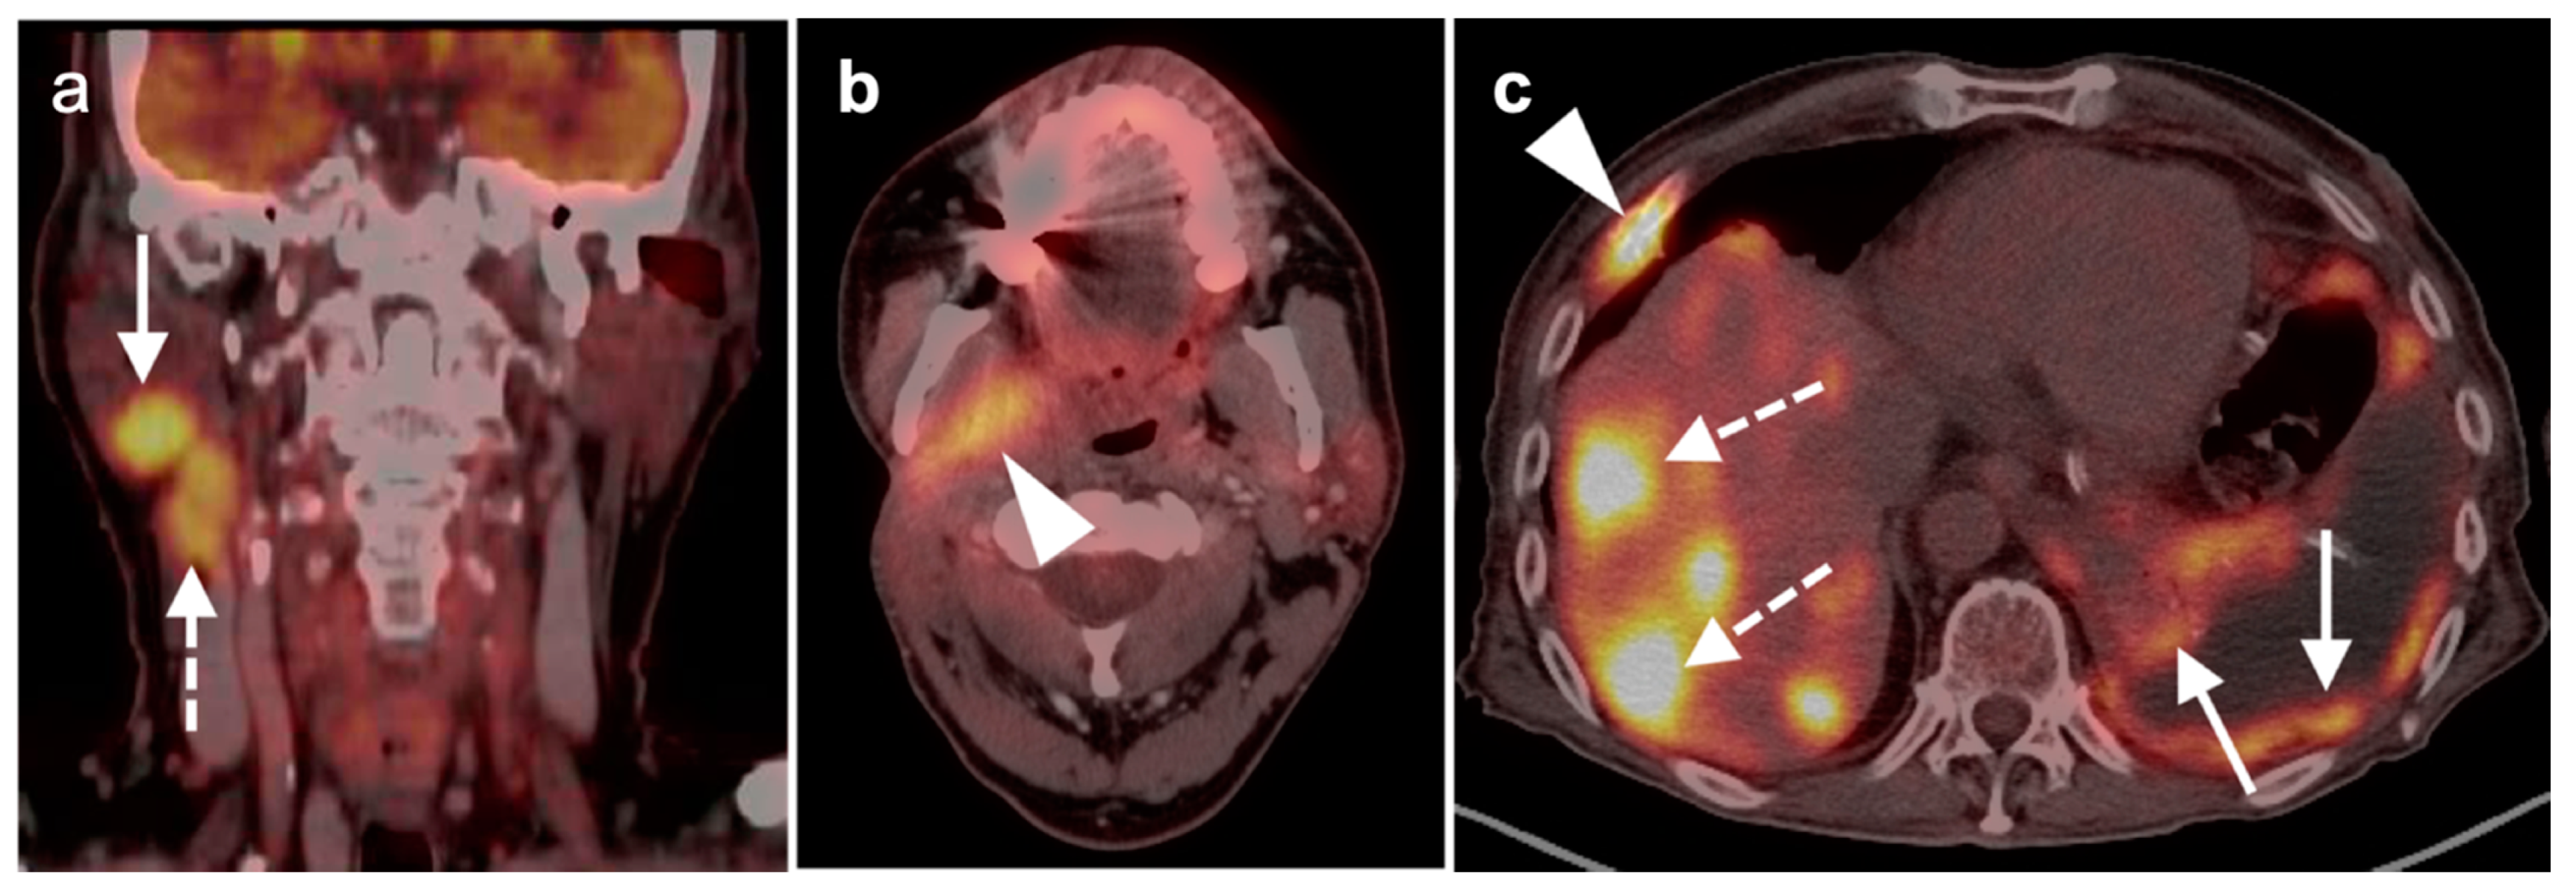

2.3. Nasopharyngeal Carcinoma